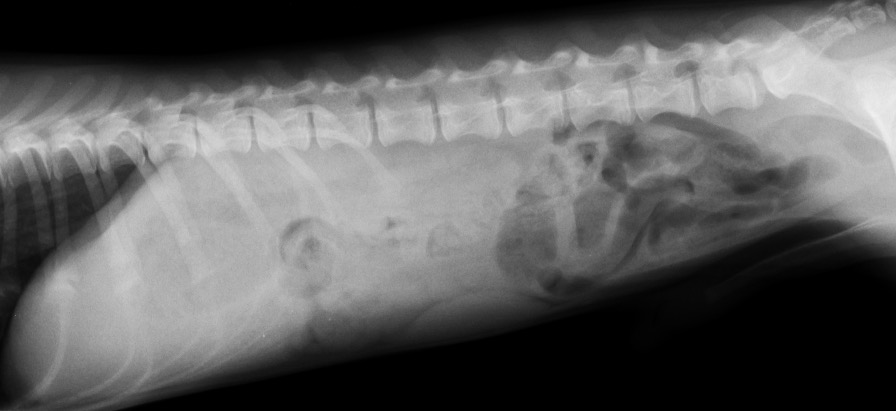

レントゲン検査 下腹部に異常な消化管のガス貯留所見